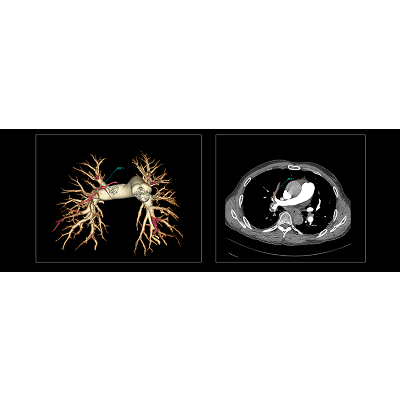

联影智能CT肺栓塞智能分析系统能够提供PE分诊预警、栓子检出和量化、肺血管智能分割和重建等功能,帮助医生及时诊断PE,鉴别诊断急性胸痛患者。同时,肺栓塞智能分析系统能够自动、准确地进行心室测量和肺动脉测量,提示右心室增宽和肺动脉增宽等PE相关风险征象,为早期PE检测和风险分层提供参考,辅助医生制定更优的诊疗方案,改善预后。

联影智能CT肺栓塞人工智能可一键智能分割、重建完整肺血管和栓子,360°展示肺动脉走行和栓子分布位置;高灵敏检出和定位栓子,提供量化分析,并自动计算RV/LV和PA/Ao,全面辅助诊疗,为PE的早期识别和临床风险分层提供强有力的智能工具;而快速分诊预警更是能够助力危急患者尽早进入诊疗环节。此外,AI可智能生成文本报告和归档图像,支持一键胶片打印。通过对救治全流程的加速优化,AI能够辅助医生快速识别隐匿肺栓塞,让胸痛患者跑赢生死竞速。